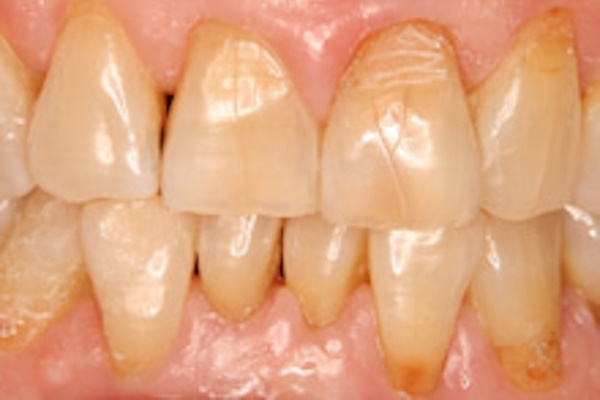

歯のすり減り

症状が進行すると、表面のエナメル質が削れて歯の中の象牙質が見えてきてしう場合もあり、虫歯や知覚過敏を引き起こしてしまう原因になります。